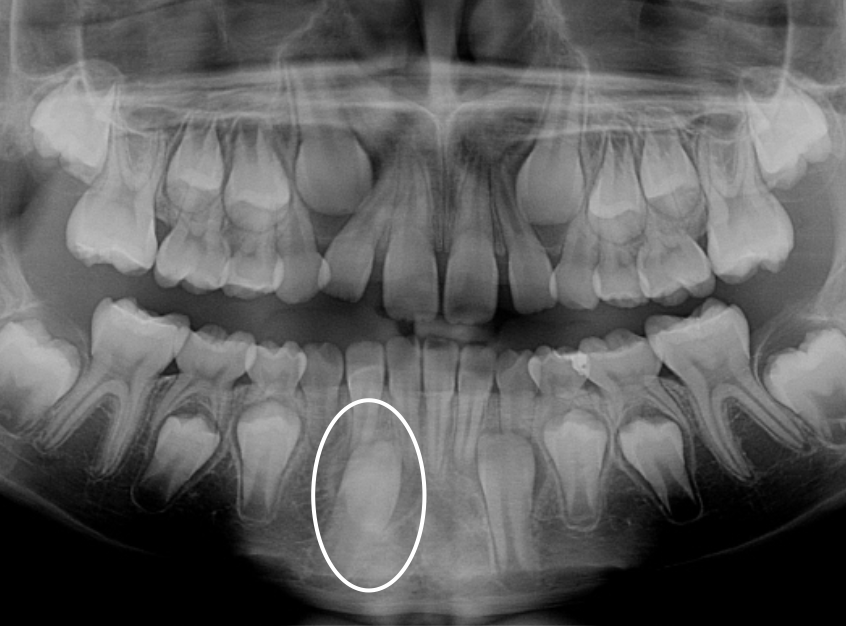

Ectopic Eruption

Ectopically erupting maxillary molar